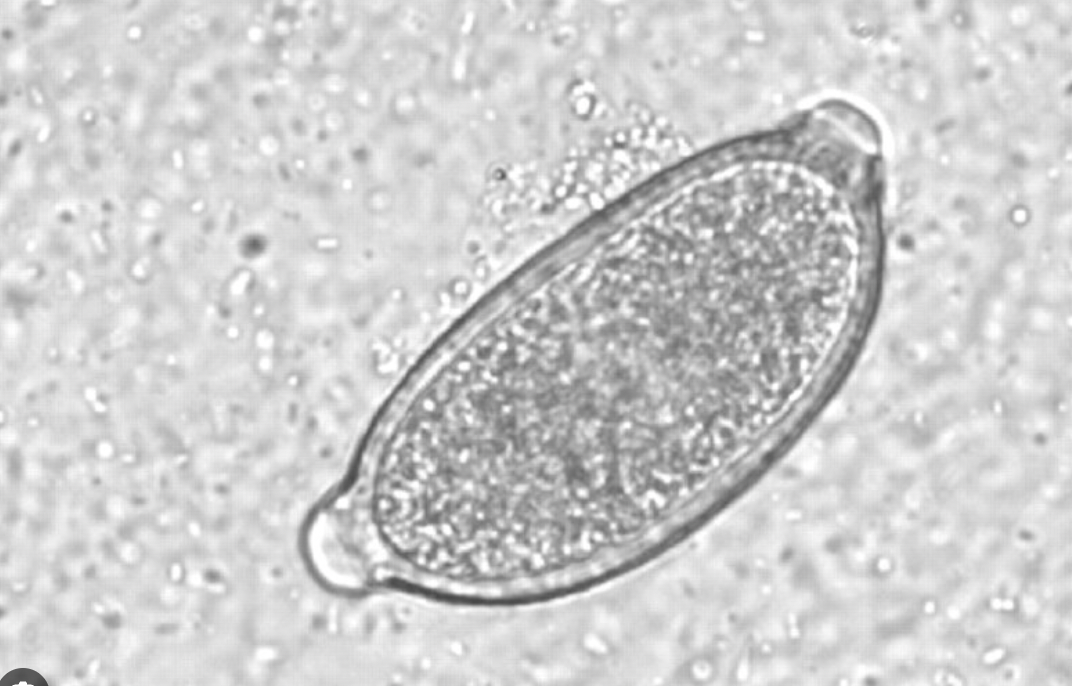

Egg Morphology Distinction:

Eggs often confused with Trichuris (whipworm) eggs; notable differences include:

Size (smaller than T. vulpis)

Color (lighter)

Shape (more broadly barrel-shaped with asymmetric bipolar plugs).